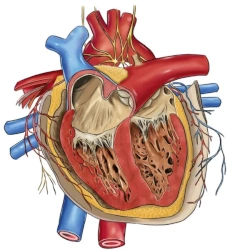

Restriktive Kardiomyopathie

Die restriktive Kardiomyopathie (RCM) ist eine schweren Funktionsstörung des Herzens (Diastole) durch zunehmend bewegungseingeschränkte Wände der Herzkammern (Ventrikel). Es kommt zu einer Herzinsuffizienz mit niedrigem Blutdruck und Ödemen.